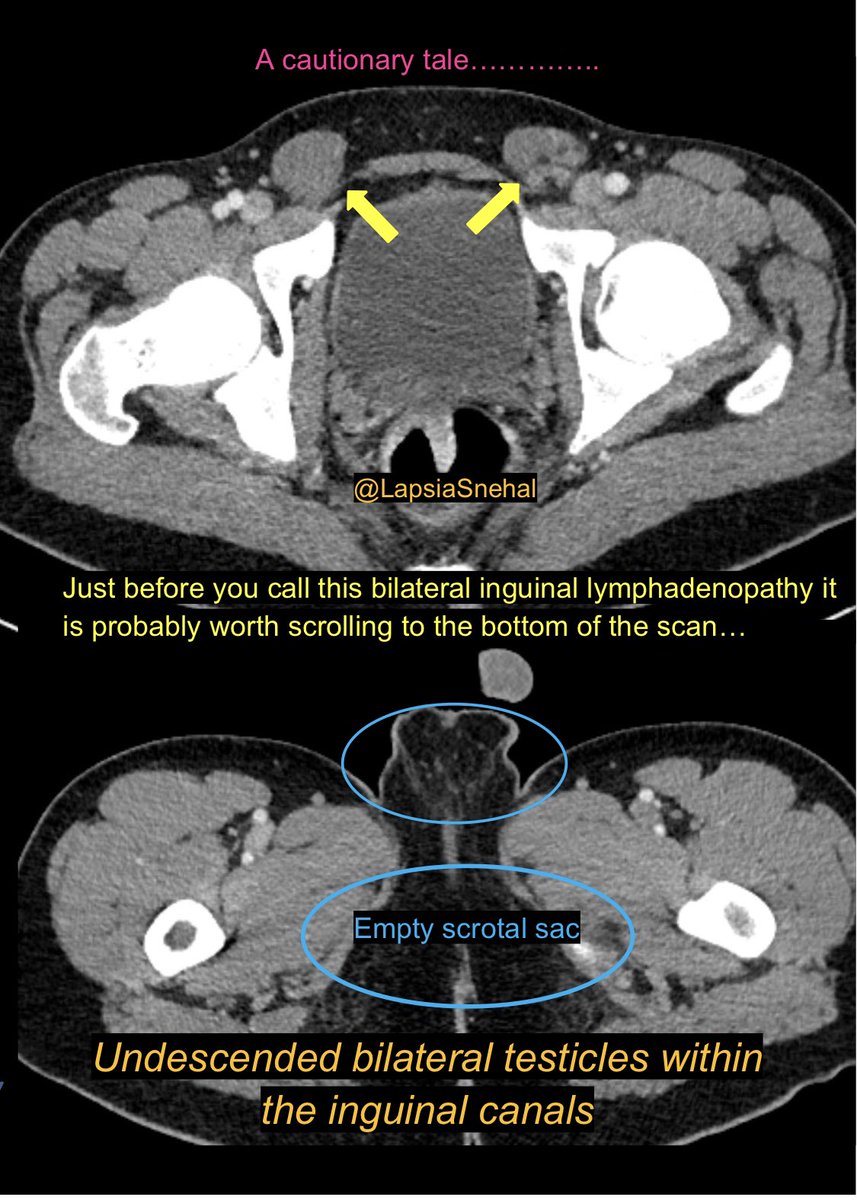

Snehal Lapsia (@lapsiasnehal) 's Twitter Profile Photo

A cautionary tale ….  #FOAMrad #FOAMed #meded  #radres #futureradres #medstudenttwitter #gitwitter #anatomy #frcr #surgery #radiology #radtwitter #medtwitter #meded #urology #irad